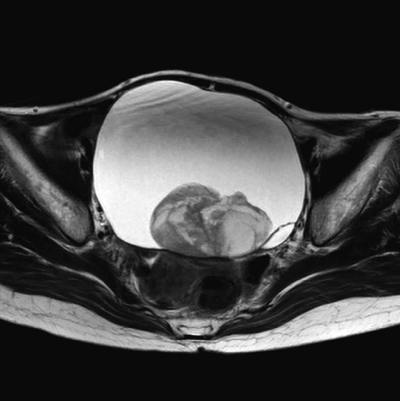

血液生化学所見:CEA 1.6 ng/mL(基準 5以下)、CA19-9 34 U/mL(基準 37 以下)、CA125 116 U/mL(基準 35 以下)。CRP 0.7 mg/dL。開腹手術を施行した。術前の骨盤部 MRI の T2 強調水平断像、矢状断像及び手術で摘出した組織の充実部分の H-E 染色標本を別に示す。

最終的な診断はどれか。

a. 明細胞腺癌

b. 傍卵巣囊腫

c. 漿液性囊胞腺癌

d. 成熟囊胞性奇形腫

e. チョコレート囊胞